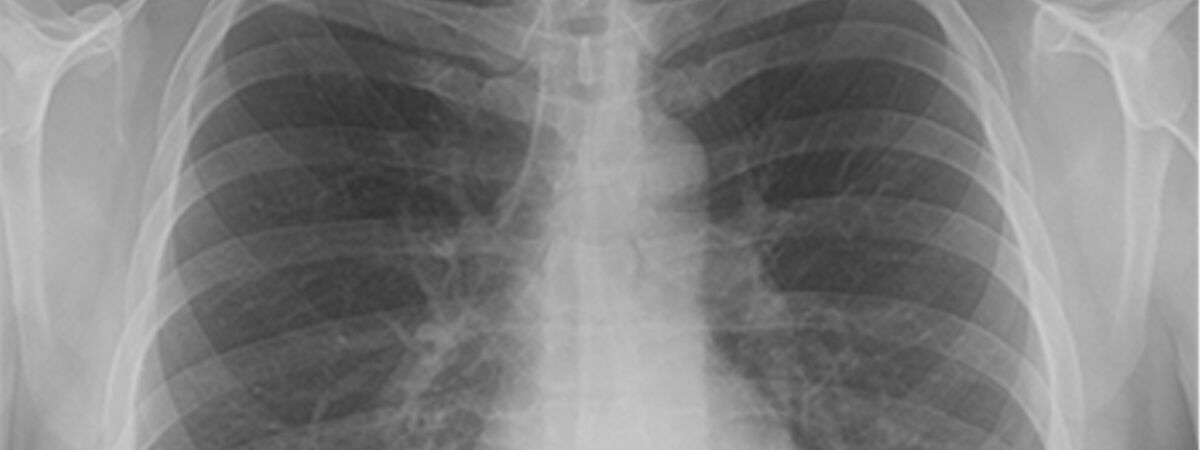

COVID-19 detection in chest x-rays

A new healthcare tool that applies artificial intelligence technology to improve the accuracy of COVID-19 detection in chest x-rays has been developed and shared by Birmingham City University researchers.

DeTraC, created by computer vision and data scientists Professor Mohamed Gaber and Dr Mohammed Abdelsamea from the School of Computing and Digital Technology, uses machine learning to assess and diagnose using large datasets of images from several hospitals across the world.

DeTraC, which stands for Decompose, Transfer and Compose, is a convolution neural network that can be trained using a limited number of medical images.